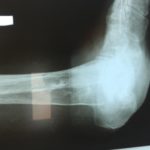

RTG przed